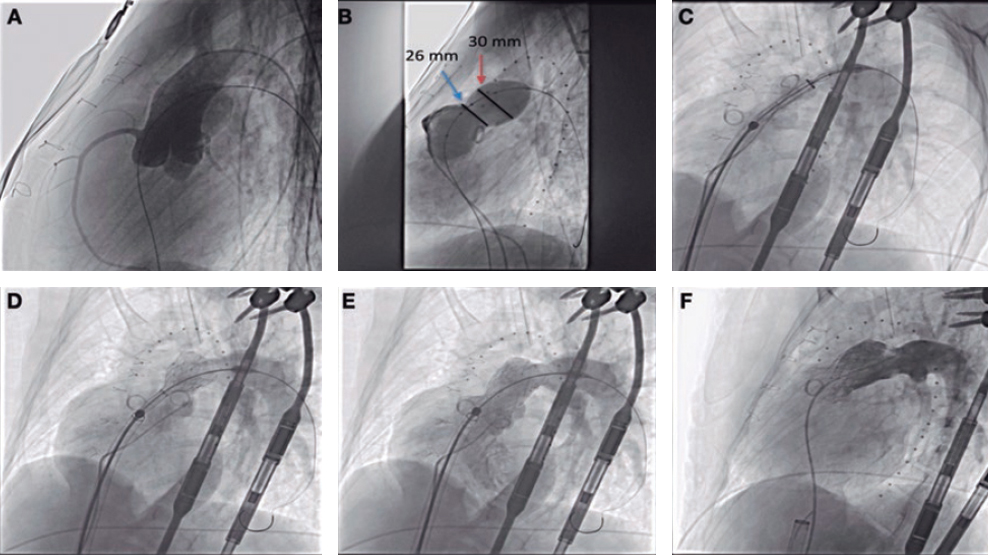

An 84-year-old female with severe aortic stenosis and previous non-disabling stroke was referred to undergo transcatheter aortic valve replacement (TAVR). The 3D computed tomography performed revealed the presence of a type 9 aortic arch with severe tortuosity (figure 1A). It was decided to protect the supra-aortic branches with suitable diameters to be able to use the Sentinel Cerebral Protection System (Boston Scientific, Marlborough, MA, United States). Manipulation length in the left common carotid artery (LCCA) was of, at least, 8 cm which is the distance between the proximal filter and the Sentinel distal edge. Figure 1B: yellow arrow: brachiocephalic trunk, 12 mm-diameter. White arrow: LCCA, 7 mm-diameter. This cerebral protection device (CPD) has a proximal filter for brachiocephalic trunk diameters between 9.0 mm and 15 mm and a distal filter for LCCA diameters between 6.5 mm and 10 mm. The angiography of the aortic arch is shown on figure 1C. This dual-system-filter basket was tried unsuccessfuly over a 0.014 in guidewire despite the use of an articulating sheath (figure 1D-F). After several attempts, a multipurpose catheter was used to engage the LCCA (figure 1G). Using a 300 cm 0.014 in guidewire, the multipurpose catheter was exchanged for the CPD which allowed its suitable deployment (figures 1H,I). The TAVR was performed successfully and the CPD was retrieved (video 1 of the supplementary data). Informed consent was obtained from the patient.

Figure 1.

The major concern is how to balance the risk of stroke after TAVR and the risk of manipulation with guidewires/catheters in supra-aortic arteries. Thus, the rigorous study of the computed tomography scan is the key factor for strategic planning purposes. This was an alternative approach to achieve the placement of a Sentinel device using a multipurpose catheter in a complex aortic arch.